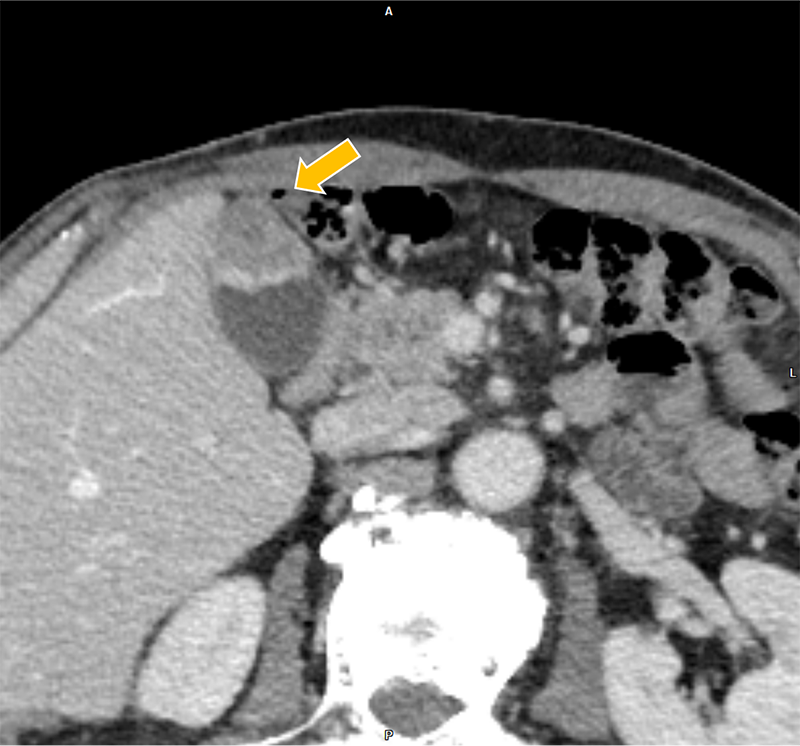

膀胱癌の治療経過観察中、胆嚢癌が疑われ、術前精査目的に肝ダイナミックCTが施行された。胆嚢底部に長径30mm程の腫瘤を認めた。また、胆嚢左側や背側にリンパ節転移を疑う造影結節を認めた。さらに、同CTで前立腺左葉から直腸左側にかけての膿瘍形成が指摘され、後の精査でBCG注入療法に伴う骨盤内BCG感染症が明らかとなった。膿瘍の治療過程で腹膜播種が出現、胆嚢癌は化学療法の方針となった。